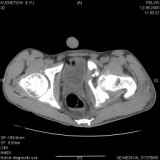

Уважаемые коллеги! Хотелось бы услышать совет по тактике лечения представлленого больного.Поступил после лечения в одном изотделений области. Травма 2,5 месяца назад. После выведенияиз шока был произведен остеосинтез перелома бедра, предплечья, до перевода к нам проводилосьвытяжение по оси шейки бедра за стержень, введенный в большой вертел. На сегодня деформацияригидна, клинически мобильности не определяется. Заранее признателен. P.S. Данный вид травм не включен в перечень "высокотехнологичных операций", направить длялечения по квотам Минздрава очень сложно.

Это обзорные и косые снимки

С уважением,

Привет, Леонид. Оскольчатый высокий двухколонный перелом в такие сроки трогать не надо, т.к. это про такие переломы сказано: "кто с ножом на Ж. пойдет тот в ней и останется...".